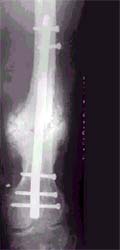

股骨骨折不愈合患者,经注射骨生长因子和骨髓细胞,6个月后骨折愈合